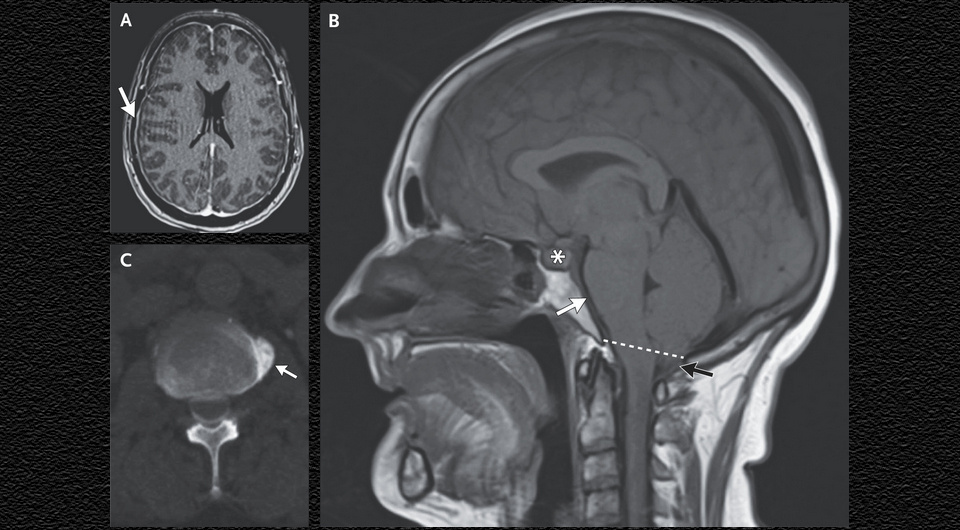

На МРТ головного мозга визуализировалось диффузное усиление сигнала от твердой мозговой оболочки. Также было видно вклинивание (эктопию) миндалин мозжечка в большое затылочное отверстие, уплощение моста мозга со сглаживанием контуров предмозговой цистерны и увеличение размеров гипофиза из-за гиперемии. Женщине выполнили компьютерно-томографическую миелограмму, которая выявила истечение ликвора из твердой мозговой оболочки на вентральной поверхности в пространстве между двенадцатым грудным и первым поясничным позвонками, вызванное остеофитом (костным наростом) позвонка на том же уровне.

Syeda Busmah Owais, Yasaman Kianirad / NEJM, 2025